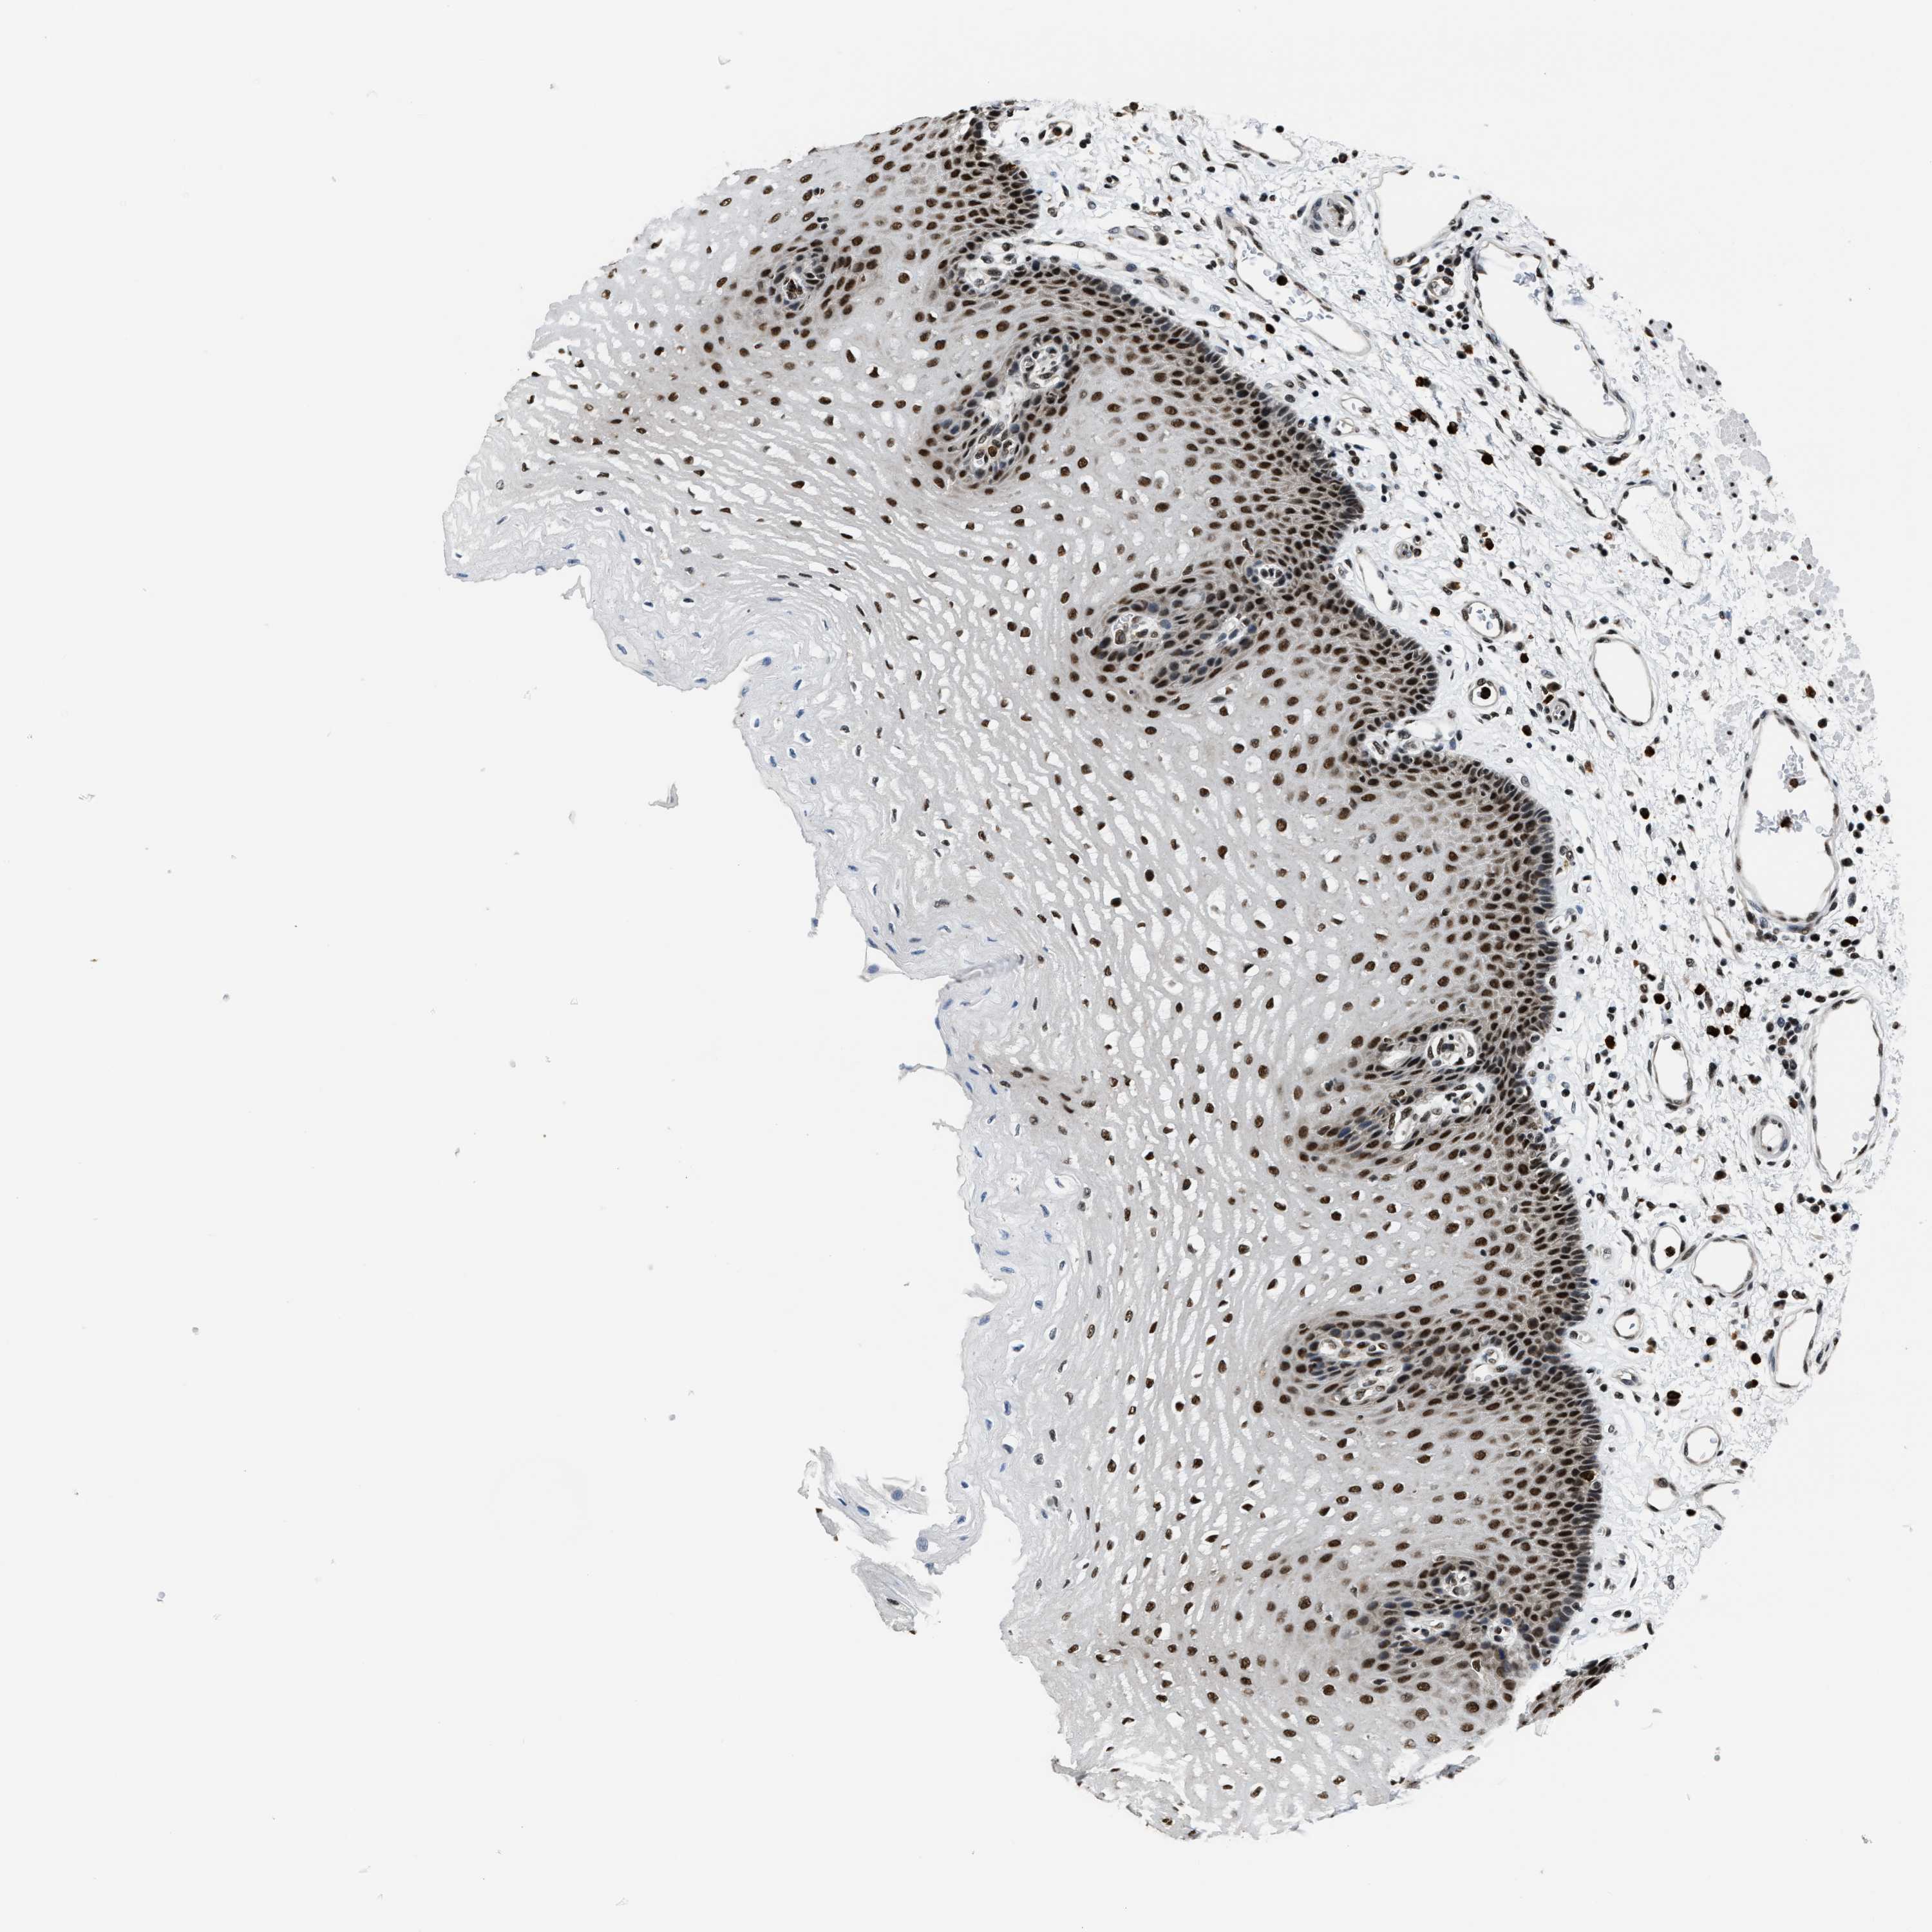

ESOPHAGUS - Antibody stainingi

Antibody staining in the annotated cell types in the current human tissue is reported as not detected, low, medium, or high, based on conventional immunohistochemistry profiling in selected tissues. This score is based on the combination of the staining intensity and fraction of stained cells.

Each image is clickable and will lead to virtual microscopy that enables deeper exploration of all samples and also displays staining intensity scores, fraction scores and subcellular localization as well as patient and tissue information for each sample.

Antibody CAB020664

Squamous epithelial cells High